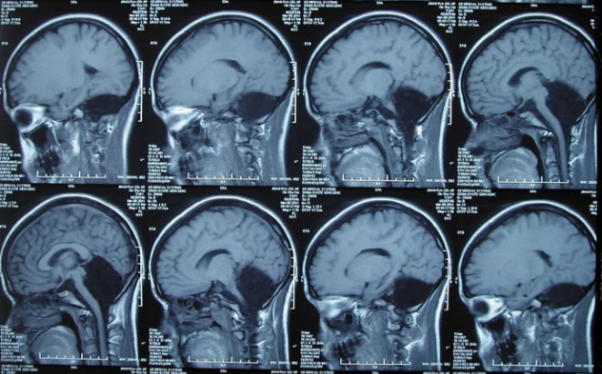

Foto z otevřených zdrojů

Normální mozková tomografie, mozeček v červené barvě